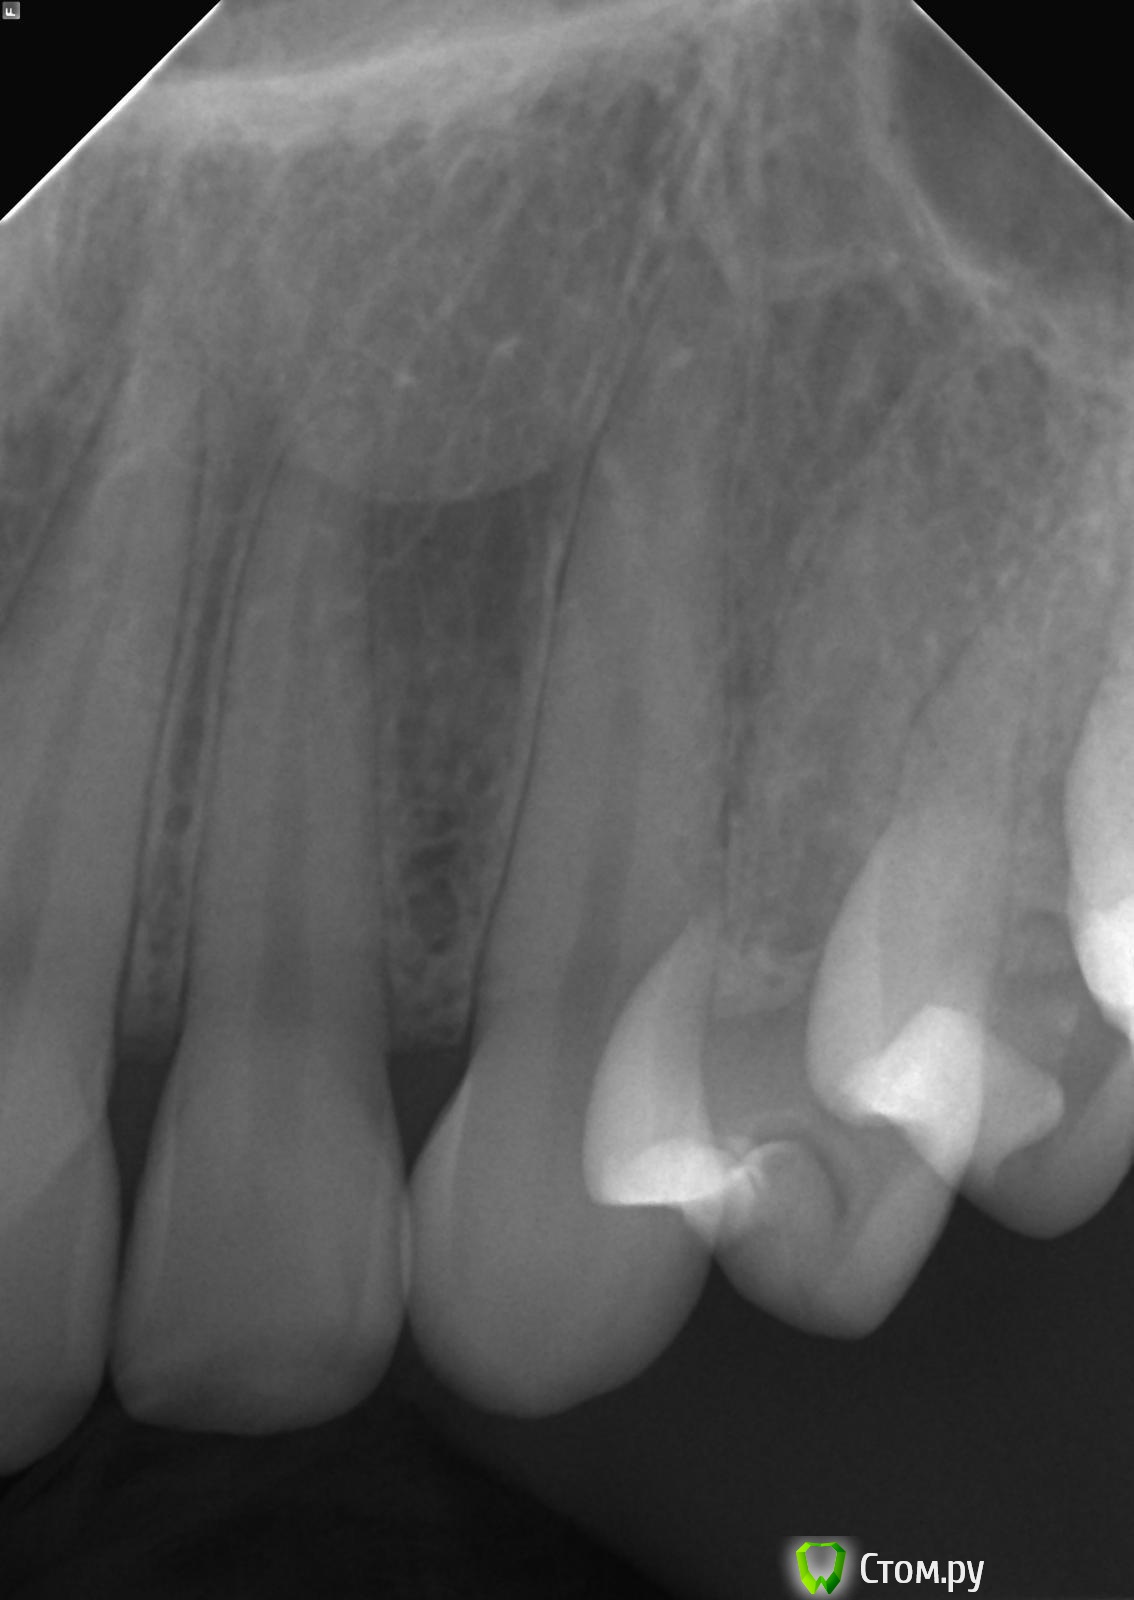

felicidade Опубликовано 25 сентября, 2014 Поделиться Опубликовано 25 сентября, 2014 Добрый день! Хотелось бы спросить мнение докторов относительно зубов 24 и 26: 1) судя по рентген-снимкам, у меня в 24 зубе кариес под пломбой. Скажите, пожалуйста, насколько он кажется близким к нерву? Может, я зря записалась к обычному терапевту, и мне надо сразу топать к эндодонту?2) зуб 26: виден ли там вторичный кариес? Я меняла пломбу в апреле этого года и заплатила то ли 5, то ли 6 тысяч за этот зуб, под прежней пломбой уже был кариес. Было бы очень обидно узнать, что новую пломбу надо снова менять Спасибо заранее и хорошего дня Ссылка на комментарий

Korel Опубликовано 25 сентября, 2014 Поделиться Опубликовано 25 сентября, 2014 По снимкам страшного ничего не вижу, приветствую Вашу запись на осмотр к терапевту, он Вам очно , думаю, ответит точнее. Ссылка на комментарий

Паращук Роман Опубликовано 25 сентября, 2014 Поделиться Опубликовано 25 сентября, 2014 То что вы можете считать кариесом,может быть не рентгенконтрастным м-ом жидкой формы. Ссылка на комментарий